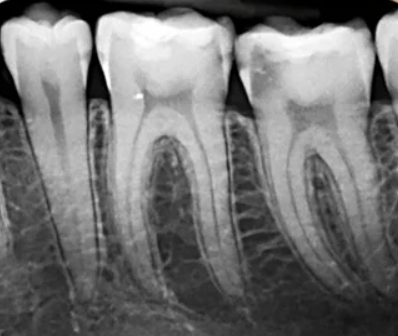

Imagen detallada de un diente específico (raíz y hueso). Permite diagnosticar problemas ocultos como caries profundas, abscesos, pérdida ósea y evaluar tratamientos como la endodoncia.